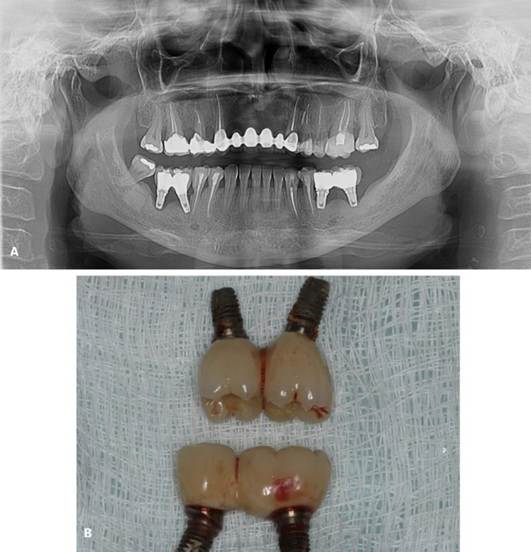

Inicialmente, o procedimento cirúrgico consistiu pela remoção dos implantes dentários (Figura 04. B), realização de enxerto imediato (Bio-Oss, Geistlinch, Wolhusen – Suíça), através da técnica de reconstrução tipo tenda, e uso da membrana de colágeno (Bio-Gide, Geistlinch, Wolhusen – Suíça). O Quadro 1 apresenta as principais medidas para avaliação do posicionamento do implante. Após 6 meses, foram instalados dois implantes dentários extra curtos ARCSYS (FGM, Joinvile – SC, Brasil) 4,0 mm x 6,0 mm x 5,0 mm do lado direito e dois implantes na região esquerda 5,0 mm x 5,0 mm. As figuras 05 e 06 evidenciam aspecto radiográfico após a etapa inicial. As recomendações pós-operatórias e a prescrição medicamentosa foram realizadas, resultando em ausência de complicações após a intervenção. O acompanhamento foi feito durante 5 anos, com resultado satisfatório (Figura 7. A – E).

Figura 05. Exames de imagem da região inferior direita. A) Vista panorâmica. B) Reconstruções tridimensionais. C) Cortes transversais oblíquos.

Figura 06. Exames de imagem da região inferior esquerda. A) Vista panorâmica. B) Reconstruções tridimensionais. C) Cortes transversais oblíquos.